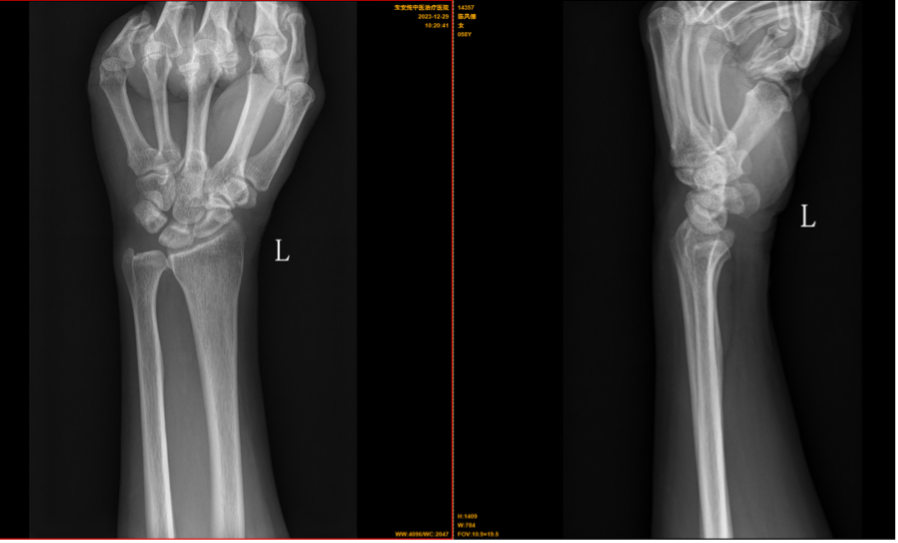

【影像】左侧腕关节正侧位片报左腕尺骨变异征阳性(关节面尺侧高于桡侧)。

【讨论】患者左侧腕背尺侧疼痛,尺骨下端向背侧突出,尺骨茎突尖端压痛(+),首先考虑三角软骨盘损伤,因患者无明确腕部扭挫伤病史,琴键试验(-),考虑尺骨撞击综合征,拍X线片以明确诊断。结果回报尺骨变异征(+),诊断为“尺骨撞击综合征”。